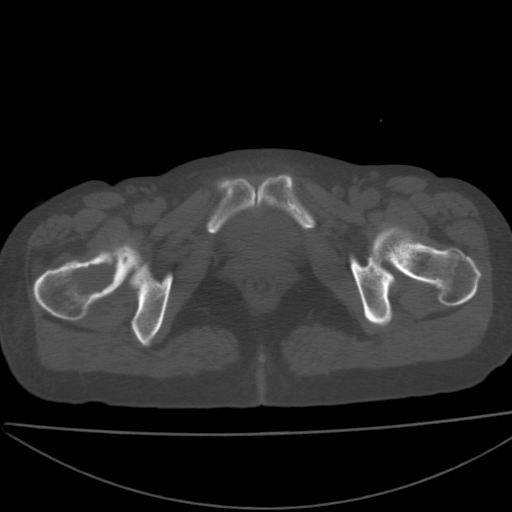

以下是引用xiaoniu在2008-9-6 8:22:00的发言:[br]右侧股骨颈囊性低密度,囊壁边缘硬化,中年妇女,首先考虑:骨囊肿。其次考虑动脉瘤样骨囊肿。[br][br][br][本贴已被 xiaoniu 于 2008-9-6 9:04:54 修改过]